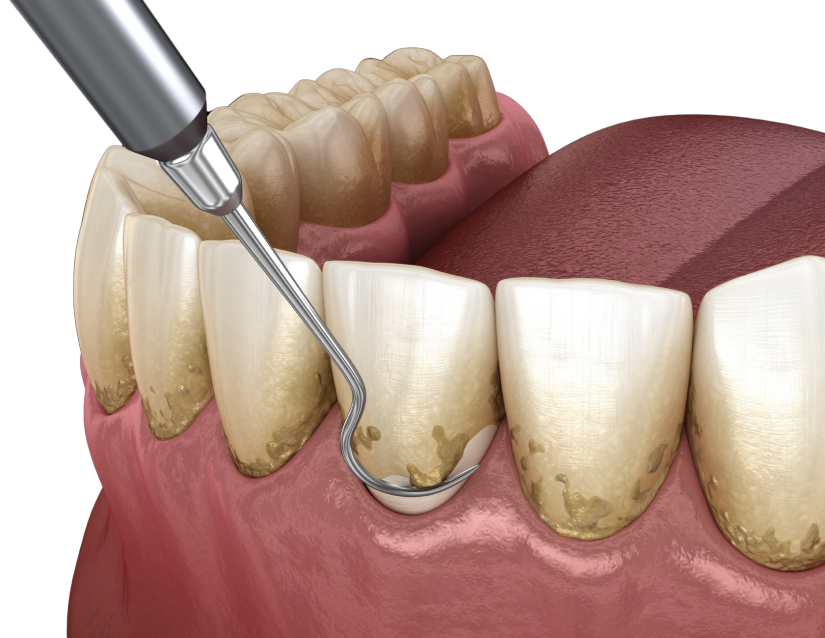

Tratamiento de Desinfección Profunda

El primer paso para detener el sangrado y la infección

Cuando las bacterias se acumulan bajo la encía, el cepillado no es suficiente. Realizamos una limpieza profunda y curetaje utilizando ultrasonido y herramientas de precisión para eliminar el sarro adherido a la raíz del diente, alisando la superficie para que la encía vuelva a sanar y adherirse firmemente.